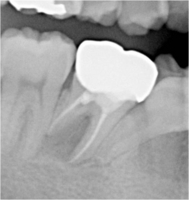

根管治療レッジ除去リカバリー症例

術前 ➡

術中

根の先に影(感染)が出てしまい根の治療を行わないといけないのですが以前他院にて処置を施した古い薬が入っています

画像を見ると手前の根にはしっかりと先まで薬が入っていません(1枚目の画像)

根のカーブに対応できず間違った方向へ削り込んでしまっています(赤矢印)

古い薬を除去しとあるテクニックを駆使し正しい根幹への道を見つけました(青矢印)

簡単にやっているように見えますがそのまま器具を入れては大きく間違った道に導かれてしまうなか、その脇から1mmにも満たない狭く曲がった孔を探しそちらへ導くのは至難の技ですが、マイクロスコープとCTを使いしっかりとした手法で行うとこのような症例にも対応できます